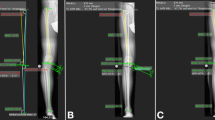

Leg alignment changes were tracked and recorded in real time using a computer navigation system (Vector Vision, BrainLAB, Munich, Germany). Minimally invasive reference arrays were attached to the femoral and tibial shafts. An isocentric mobile C-arm with 3D imaging capability (Siremobil ISO-C 3D, Siemens, Germany) was used to scan the knee joint. The imaging dataset was transferred to the navigation system, and registration was performed. The combination of the acquired 3D imaging and computer navigation data allows for real-time monitoring of the mechanical axis. Hence, we were able to follow intraoperative changes in alignment live through a computer interface.

To further monitor and confirm mechanical alignment changes after increasing the medial tibial opening, we placed a lead-impregnated axis board underneath the leg [12]. The long axis was situated through both the centre of the femoral head and the centre of the talus. Correct positioning was confirmed using fluoroscopy. Once the board was in place, subsequent fluoroscopic images were used to identify the location of the mechanical axis in relation to the centre of the knee joint and to quantify alignment changes by measuring the angle between the mechanical axis line and the tibial plafond outline.

Moderate-to-large alignment changes after medial opening-wedge HTO resulted in a significant shift in intraarticular contact pressures from the medial compartment of the knee towards the lateral compartment (pressure ratio: 1.9; P < 0.05). However, fixation of the distal tibial segment at 15° of external rotation neutralized this intended beneficial effect (pressure ratio: 1.1; P < 0.05) (Figs. 1a, b, 2). A significant increase in tibiofemoral contact area was also observed in the medial compartment (P < 0.05) (Fig. 3a, b).